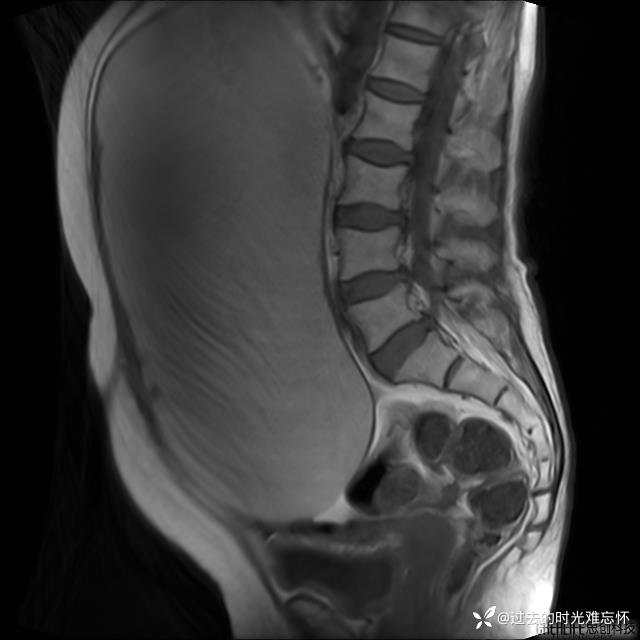

患者性别:女

患者年龄:65岁

主诉: 发现腹部隆起半年余。无其他明显不适。

浆液性囊腺瘤 (22)